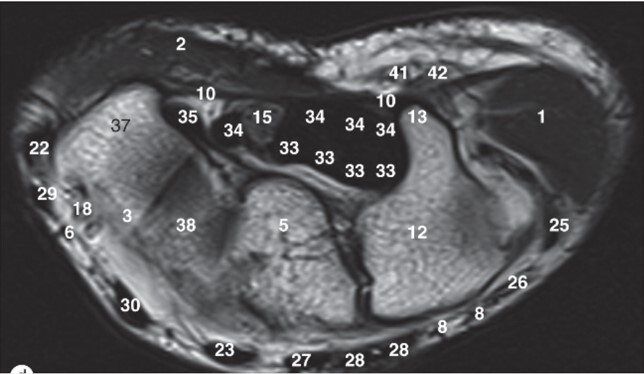

Label 5,12,13,37,38

5=Capitate

12-Hamate

13=Hook of Hamate

37=Trapezium

38=Trapezoid